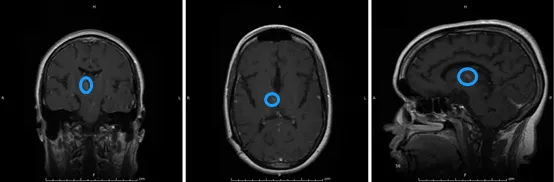

消融后3个月的磁共振成像MRI,肿瘤体积缩小了70%